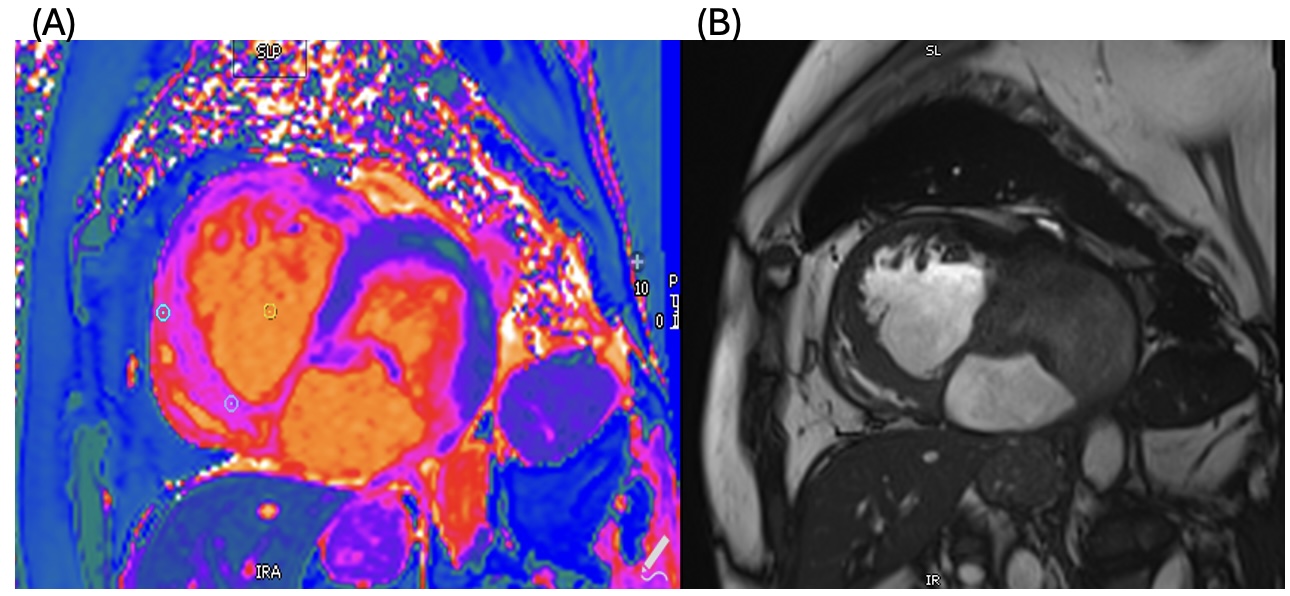

Fig 2. Steady-state free precession (SSFP): Two-chamber view showing communication between the ventricular cavity and the pseudoaneurysmal sac.